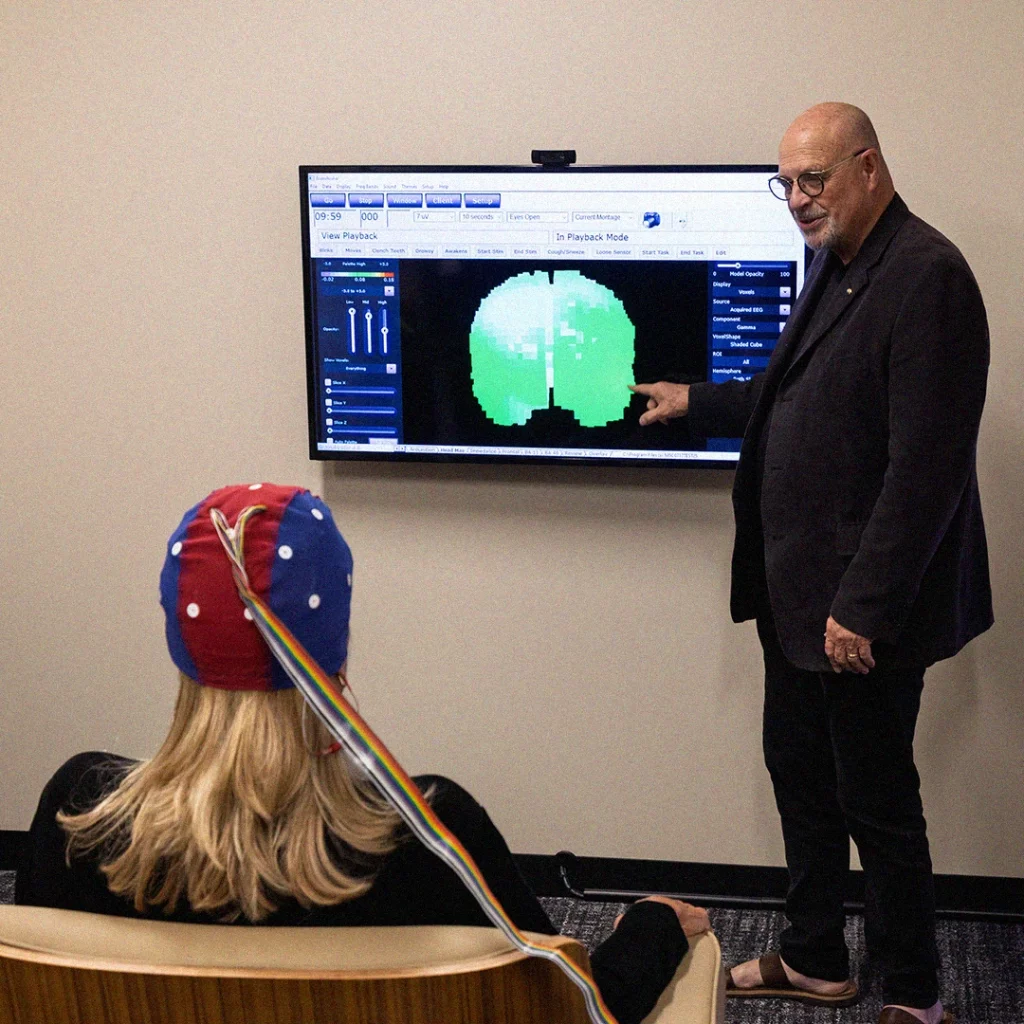

How Does It Work?

Proven 3-Step Process for Brain Performance Enhancement

We combine cutting-edge neuroscience and EEG scanning with practical, real-world applications to achieve measurable improvements in your brain’s performance. Through research-backed TTI assessment tools, we measure individuals’ behaviors, what motivates them, their emotional intelligence, and stress levels.

Led by Dr. Ron Bonnstetter

Dr. Ron Bonnstetter, a global leader in brain science and human behavior, directs The MindScience Center. His decades of research, coupled with TTI Success Insights’ assessment tools, make this program a unique opportunity for executives to optimize their brain performance and leadership abilities.